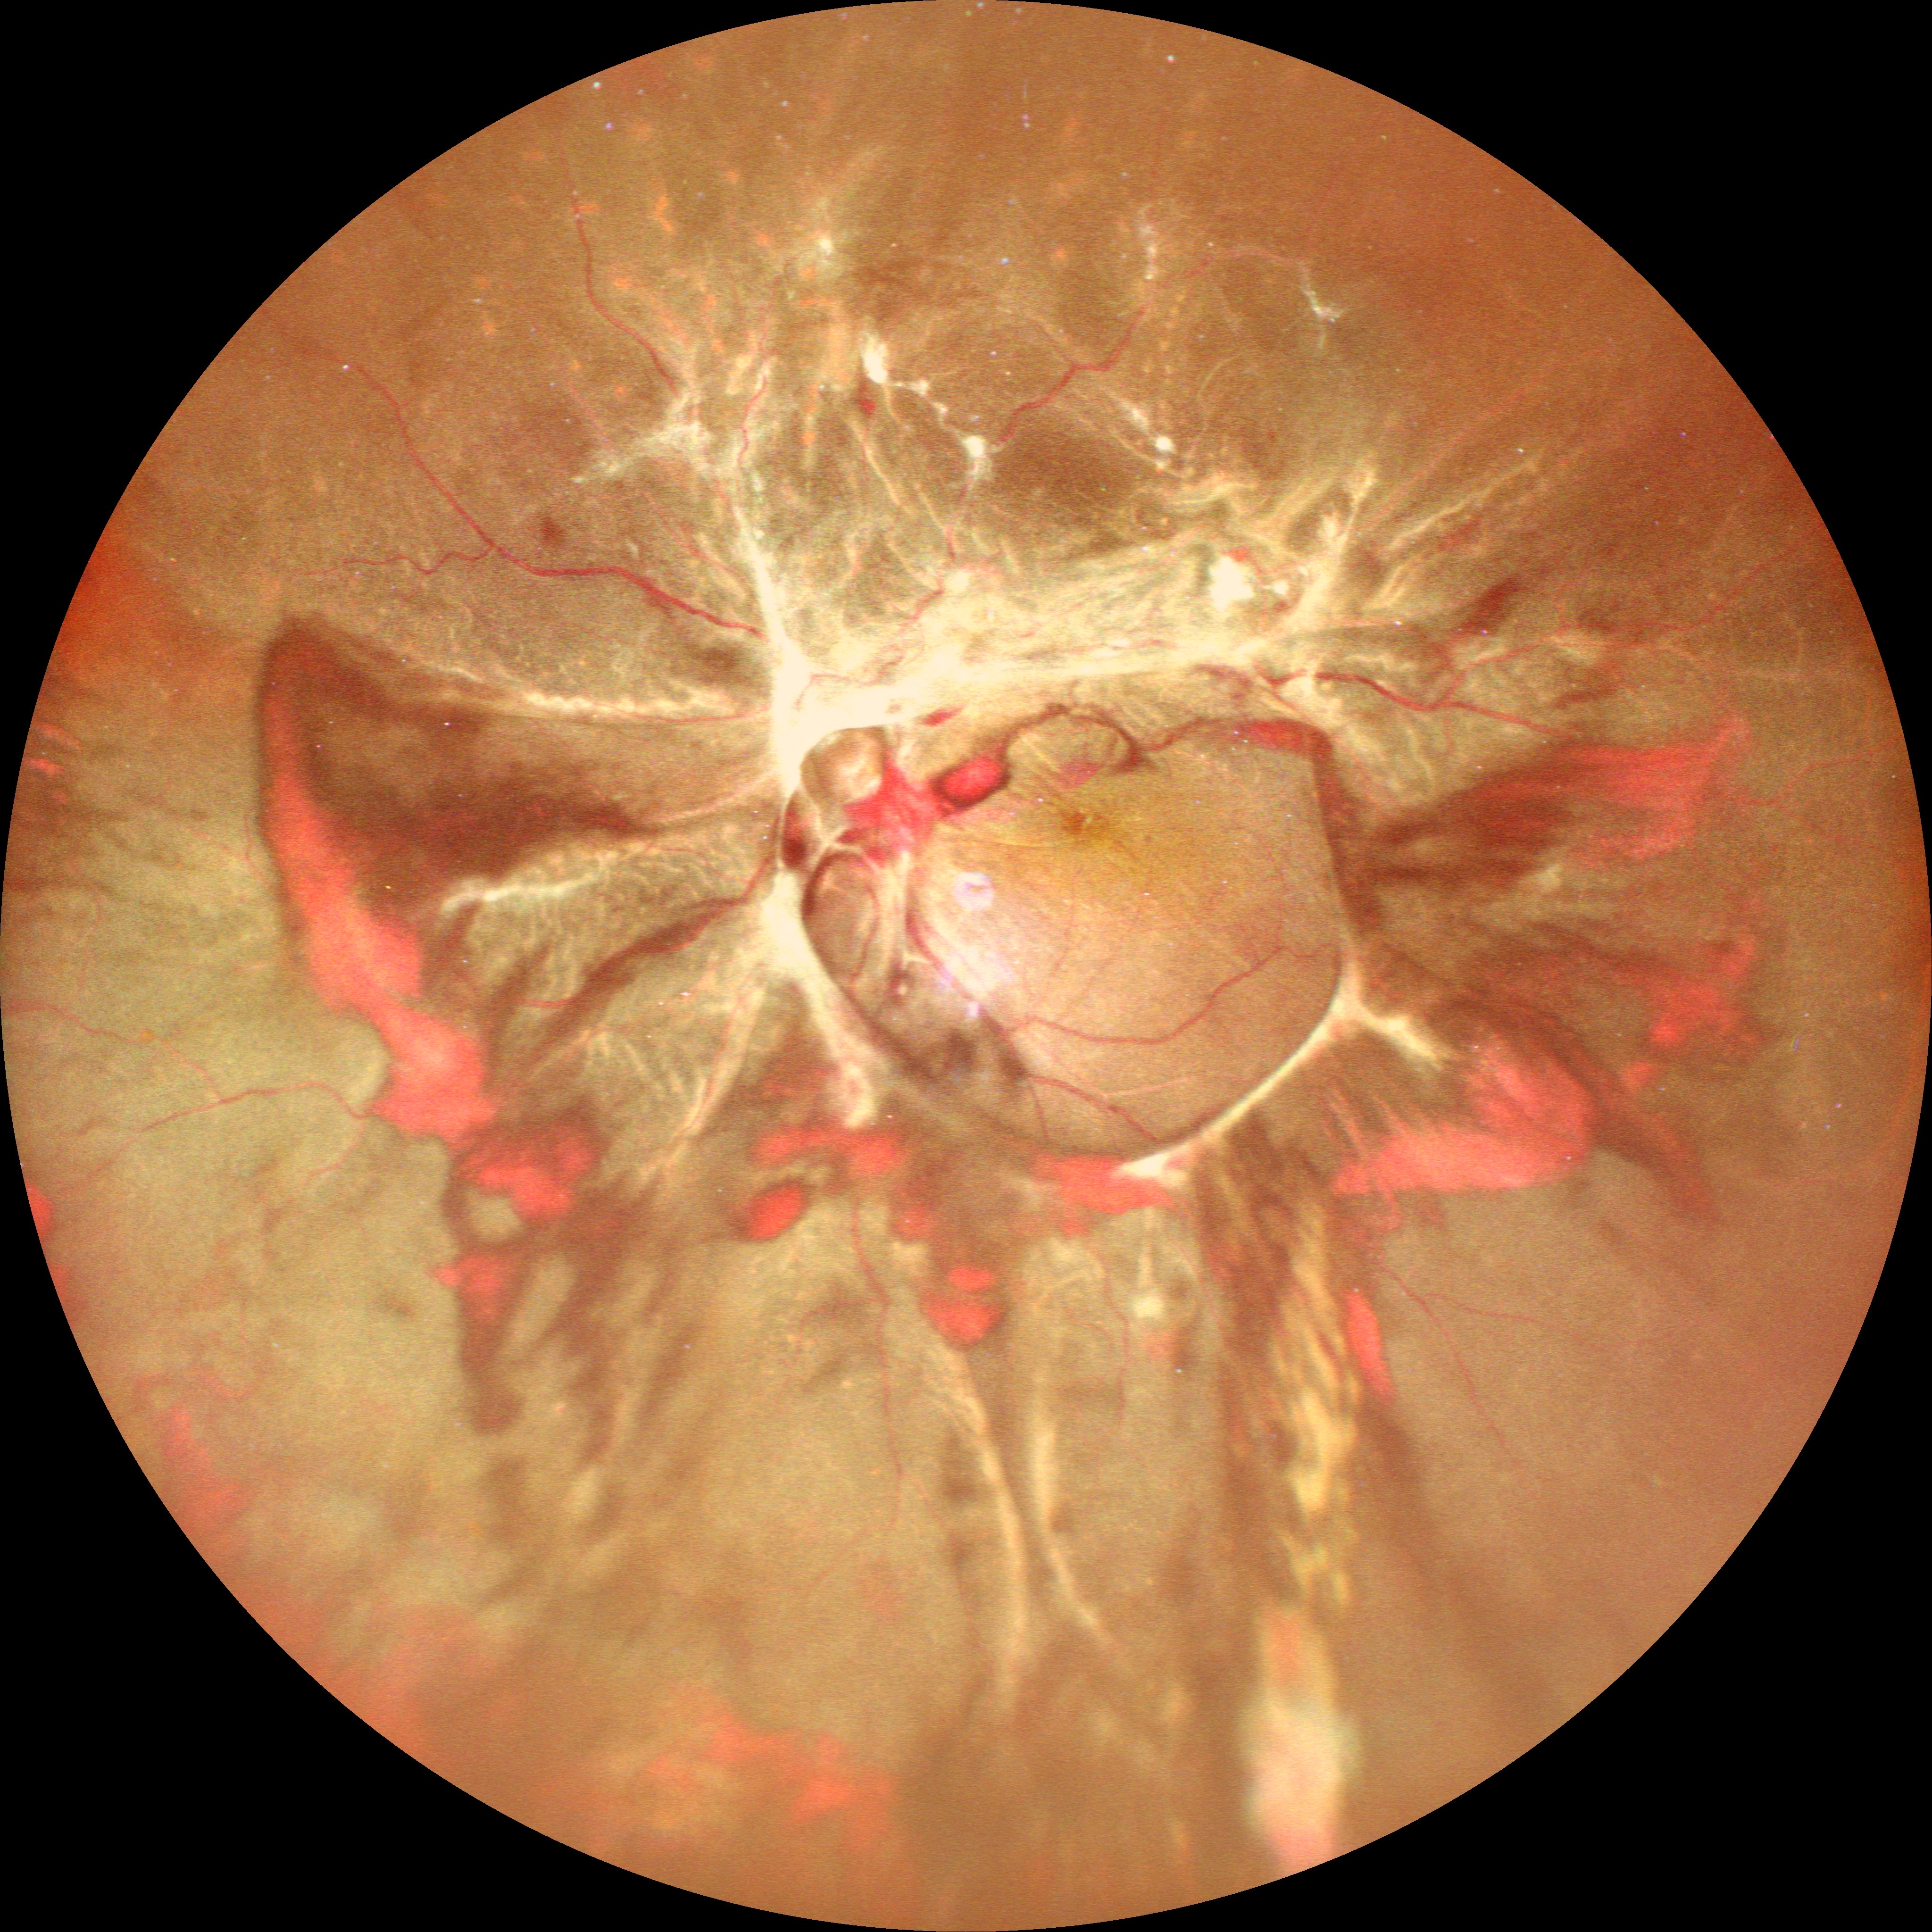

治療在PDR合并玻璃體出血和TRD的診斷下,患者接受玻璃體切除手術,剝除纖維血管增生膜,并行全視網膜光凝,硅油填充。1個月后,視網膜貼附良好(圖2),左眼BCVA提高到20/100。

圖2. 經玻璃體切除術并行全視網膜光凝及硅油填充治療后,在Mirante超廣角圖像可見視網膜貼附良好。